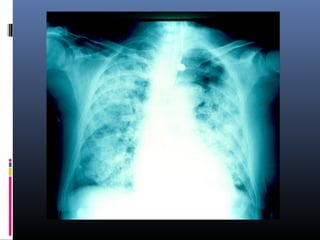

NEUMONIA POR PNEUMOCISTIS

CARINII Enfermos inmunodeprimidos.

 Complicación principal en px con S.I.D.A.

 Es frecuente infiltrados difusos confluentes.

Síndrome de GoodPasture (Hemorragia pulmonar por nefropatía)

Opacidadesmoteadasdifusas,zonasdeconsolidaciónbilateralesdiseminadasde

modouniformeenamboscampospulmonares,confluyentes.Seconservanángulos

costodiafragmáticosindemnesaligualquelaszonasapicales.Adenomegalias

parahiliaresderechas.